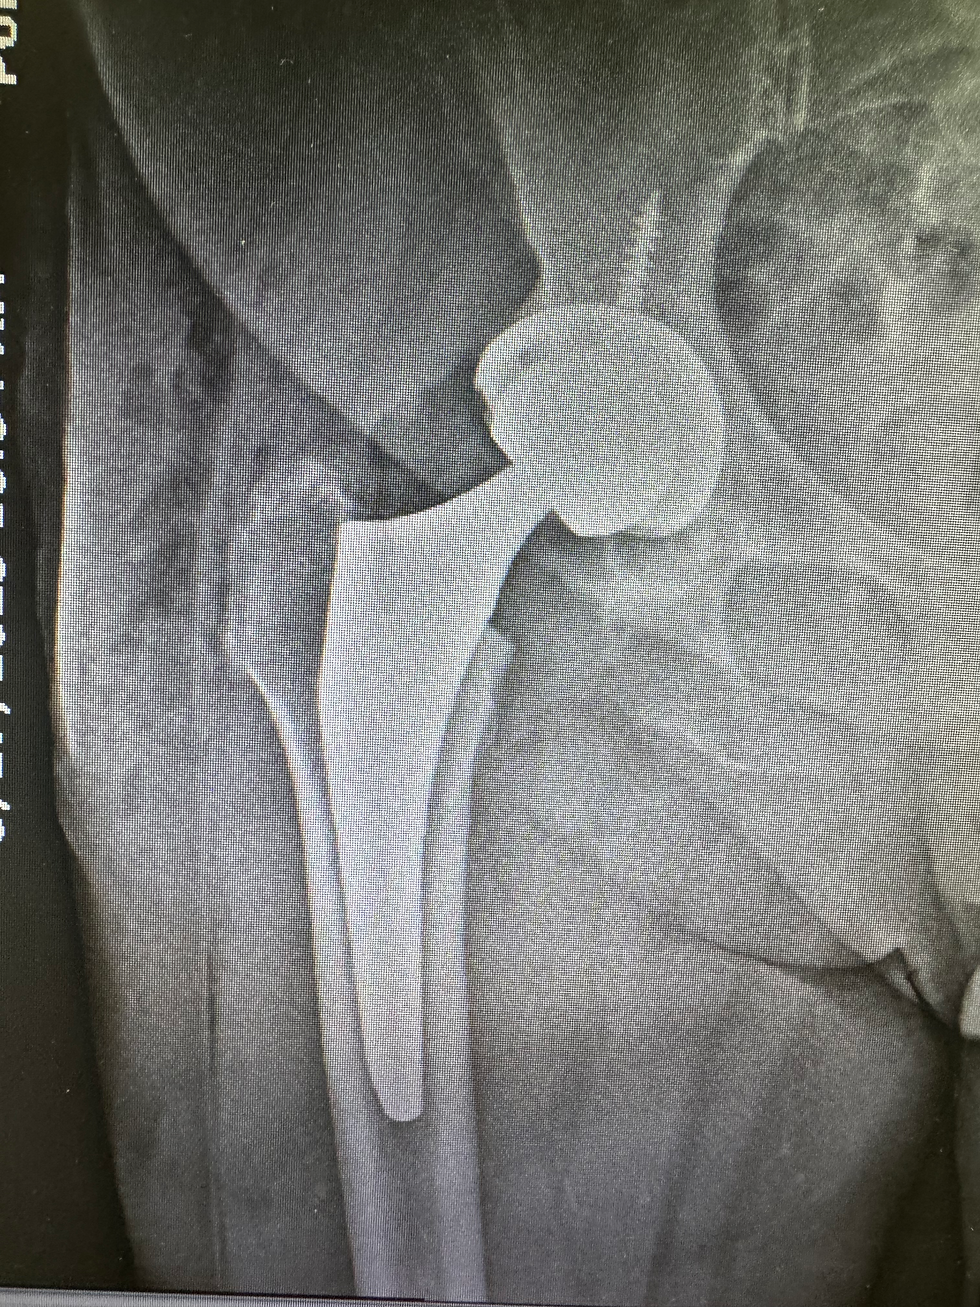

Reemplazo Total de Cadera

En pacientes con artritis avanzada o daño severo, el reemplazo total de cadera suele ser la mejor opción. Los implantes modernos ofrecen excelentes resultados, reducen el dolor y restauran la movilidad.

Después de un reemplazo total de cadera: muchos pacientes caminan a los pocos días, retoman actividades cotidianas en semanas y logran alivio duradero del dolor.